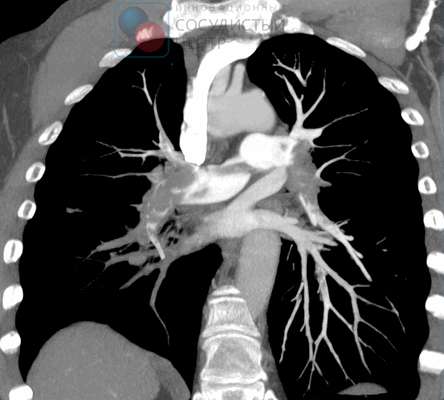

Компьютерная томография и КТ-ангиопульмонография

Основными задачами ангиографической диагностики являются определение степени тяжести легочной гипертензии, уточнение характера поражения легочного русла посредством ангиопульмонографии, выявление/исключение коронарной болезни. Проведение катетеризации в изолированном виде без качественной ангиопульмонографии у больного с четкими признаками ХТЭЛГ нецелесообразно. Это исследование должно дать четкую информацию врачам для решения вопроса об операбельности больного и тяжести его состояния. Гемодинамическими критериями постэмболической легочной гипертензии, выявляемыми при катетеризации правых отделов сердца, являются: среднее давление в легочной артерии (ДЛА) выше 25 мм рт. ст., давление заклинивания легочной артерии (ДЗЛА) ≤ 15 мм рт. ст., ЛСС > 2 ЕД. по Вуду (160 дин. сек см- 5 ) при наличии множественных стенозирующих и/или окклюзирующих поражений ветвей легочной артерии различного калибра.

- Компьютерную томографию - послойные снимки органов грудной клетки показывают увеличенные легочные артерии, а также сопутствующие легочной гипертензии заболевания сердца и легких.

- Рентгенографию легких - определяет выбухание главного ствола легочной артерии, расширение ее главных ветвей и сужение более мелких сосудов, позволяет косвенно подтвердить наличие легочной гипертензии при выявлении других заболеваний легких и сердца.

- Катетеризацию легочной артерии и правых отделов сердца - проводится с целью определения кровяного давления в легочной артерии. Является самым достоверным методом диагностики легочной гипертензии. Через прокол в яремной вене зонд подводится к правым отделам сердца и с помощью монитора давления на зонде определяется кровяное давление в правом желудочке и легочных артериях. Катетеризация сердца является малоинвазивной методикой, практически не сопряженной с риском осложнений.

- Ангиопульмонографию - рентгенконтрастное исследование сосудов легких с целью определения сосудистого рисунка в системе легочной артерии и сосудистого кровотока. Проводится в условиях специально оснащенной рентгеноперационной с соблюдением мер предосторожности, т. к. введение контрастного вещества может спровоцировать легочно-гипертонический криз.